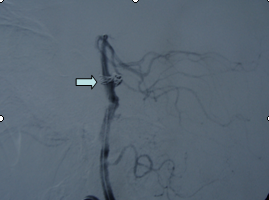

吴某,56岁,因突发昏迷1小时于2月15日急诊入院。入院时深昏迷,呼吸微弱,血氧和血压降低,双侧瞳孔散大,对光反射迟钝,急诊头颅CT提示蛛网膜下腔出血。入院诊断考虑是脑动脉瘤破裂,紧急行气管插管、止血降颅压等抢救措施,同时放射科陆秀伟主任急诊行全脑血管造影,结果提示基底动脉巨大的动脉瘤(图一)。科主任范学政教授紧急组织全院会诊,组成了包括神经外科、重症医学科、呼吸科、放射科专家抢救小组,采取镇静、脱水、抗血管痉挛以及支持和对症等抢救措施,并病情和影像资料传输到神经外科协助医院四川大学华西医院神经外科远程会诊,会诊认为该病人最佳的治疗方案是行血管内介入治疗。经过充分准备,于2月19日在华西医院神经外科张昌伟教授联合我院神经外科医生为患者进行了支架辅助下基底动脉瘤弹簧圈栓塞术,术后行脑血管造影显示动脉瘤完全栓塞(图二)。术后继续予抗血管痉挛等治疗,术后第二天出现呼吸衰竭,肺部感染,后经转入ICU、呼吸科、予以支持、抗感染治疗等综合治疗,术后10天病人清醒,目前患者已经康复出院。

图1:基底动脉瘤